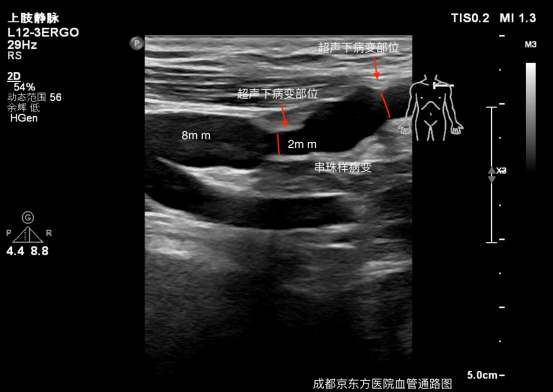

检查发现:我们这位患者有一个大吻合口、单一回流途径、血透龄超过 3 年的自体动静脉内瘘,这也是头静脉弓常见病变原因。成都京东方医院血管通路 MDT 团队经讨论采用了目前治疗首选方法超声引导下 PTA(经皮腔内血管成形术)。穿刺入路为同侧上肢通路静脉,使用 0.035 超滑导丝顺行通过头静脉弓狭窄,采用逐级扩张策略行球囊扩张。术后震颤增强,血流量:240 ml/min,高通量透析器,透析 4 小时,kt/v:1.41,URR:69.7%。